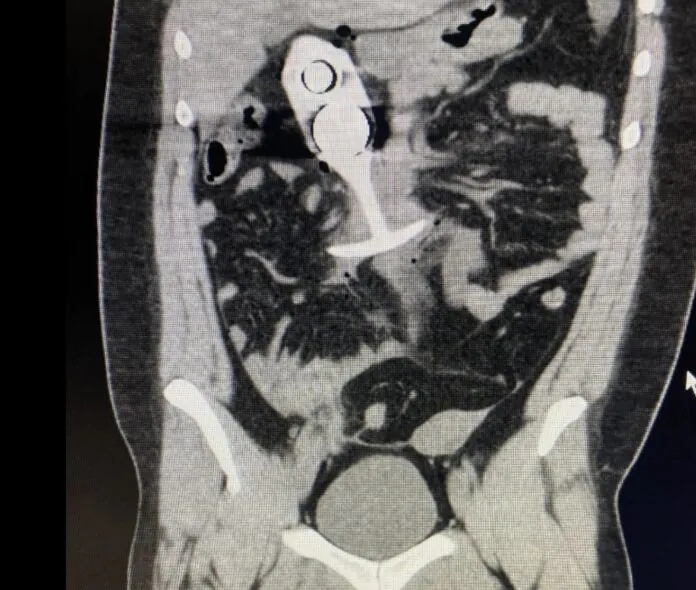

Le noyau métallique de son sextoy a violemment réagi au champ magnétique ultra-puissant de l’IRM et a entamé une ascension express depuis son point d’insertion initial anal jusqu’à sa cage thoracique. Un véritable tremplin anatomique, digne d’une compétition de sports extrêmes, voire d’un grand huit médical.

Dans le cas de Madison, le plug anal aurait atteint une vitesse instantaée proche de celle du son (1235 km/h !) à l’intérieur de son corps !

Après avoir été extirpée en urgence de la machine, Madison a été transportée en soins intensifs. Le plug express avait causé des lésions internes importantes mais, par un rare miracle, aucun organe vital n’a été perforé.

Les chirurgiens ont cependant dû intervenir pour extraire l’objet et soigner les traumatismes internes. D’après les premières analyses médicales, si la vitesse avait été un peu plus élevée, Madison aurait pu subir des blessures mortelles. Une IRM peut en effet transformer un simple objet métallique en projectile létal.